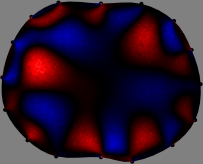

Figs. 3 and 4 compare the performance of the proposed FER method in (20) with the standard regularized least-squares method ((19) when \mathcal{R} is the identity matrix). The regularization parameter of the standard method was heuristically chosen for its best performance, and the parameter of the FER method was set to be one of three different values λ=0.05,0.2,𝜆0.050.2\lambda=0.05,0.2,\infty. The injection current was 1 mARMSRMS{}_{\tiny{\mbox{RMS}}} at 100 kHz, and the frame rate was 9 frames per second. The reference frame at t0subscript𝑡0t_{0} was obtained from the maximum expiration state. The measured data, 𝐕˙(tm)˙𝐕subscript𝑡𝑚\dot{\mathbf{V}}(t_{m}), represent the voltage differences between each time tmsubscript𝑡𝑚t_{m} and t0subscript𝑡0t_{0}. The blue regions, which denote where conductivity decreased by inhaled air, increased during inspiration and decreased during expiration. The FER method with λ=𝜆\lambda=\infty was clearly more robust than the standard method that produced more artifacts originated from the inversion process.

Figure 3: The reconstructed images of the conductivity change of the subject A by the standard regularized least square method and the proposed fidelity-embedded regularization (FER) method for three difference values λ=0.05,0.2,𝜆0.050.2\lambda=0.05,0.2,\infty. Here, the time step is 0.22 seconds (tm+2tm0.22subscript𝑡𝑚2subscript𝑡𝑚0.22t_{m+2}-t_{m}\approx 0.22).